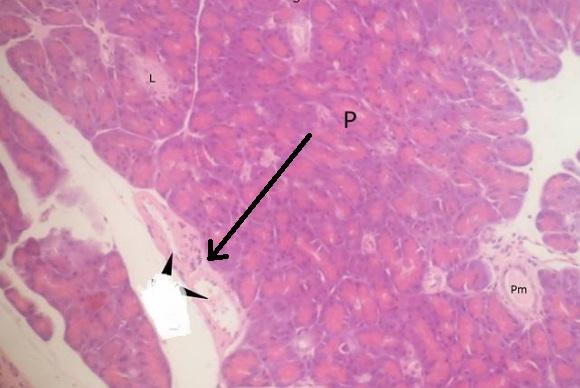

wyspa Langerhansa (trzustka)

pęcherzyk surowiczy (trzustka)

przewody śródpłacikowe - wstawki z nabłonkiem jednowarstwowym walcowatym (trzustka)

przewód międzypłacikowy z nabłonkiem jednowarstwowym walcowatym (trzustka)

przewód międzypłacikowy - z tkanką łączną dookoła (trzustka)

naczynia krwionośne (trzustka)

przegroda międzyzrazikowa (trzustka)